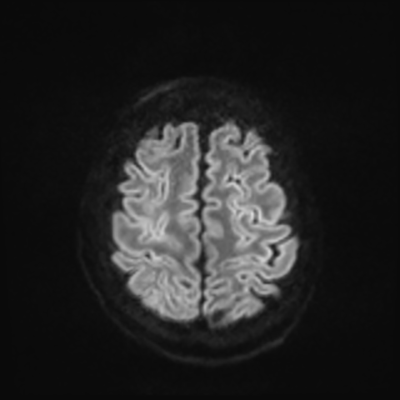

MRI brain (DWI)

You can clearly see diffuse cortical and basal ganglia diffusion restriction, and that of his deep cerebellar nuclei as well. The right occipital lobe abnormalities are a little more prominent, but then you remember that he is known to have had a right occipital stroke weeks ago.